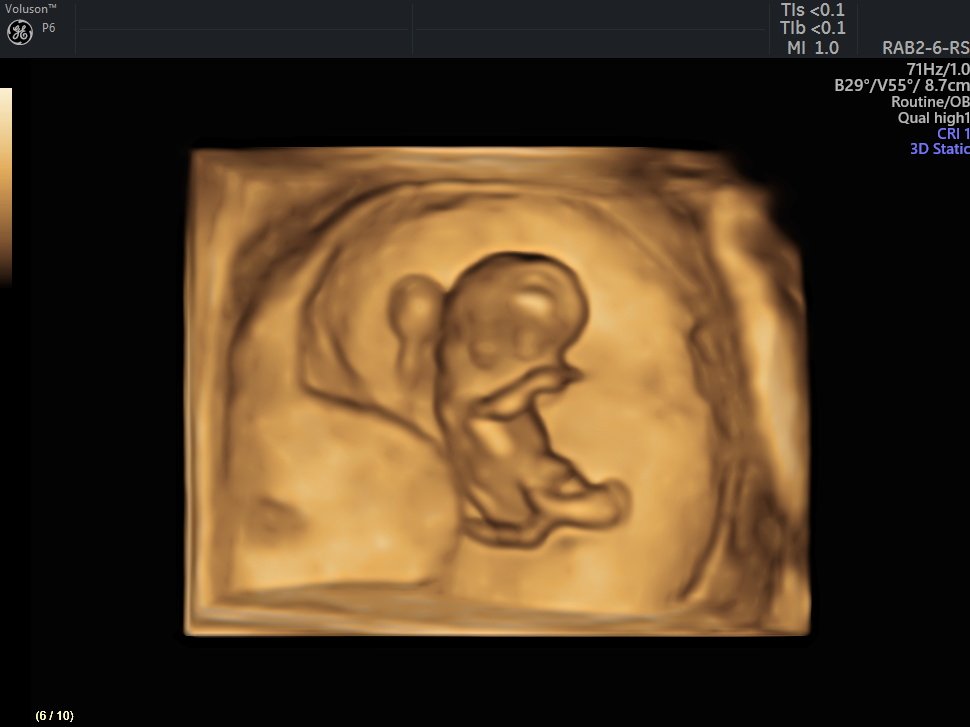

4 Boyutlu (Renkli) Ultrason ve Doppler Ultrasonografi

Gebelik sürecinde Fetüsün gelişimi

4 D Ultrasonografi